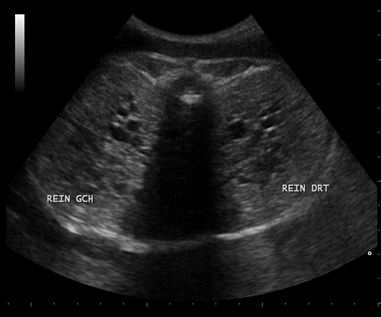

A 20-year-old female G1P0 presented to the obstetric department for the first time, with history of 28 weeks amenorrhea for routine antenatal examination. There was history of third-degree consanguineous marriage. She had her antenatal examination at a peripheral hospital. She was taking iron and folic acid (dosages of iron and folic acid were normal). Ultrasound done at our hospital as a routine, revealed a fetus with occipital meningocele (Figure 1), bilateral enlarged echogenic kidneys (Figure 2), polydactyly, and severe oligohydramnios. We found no liver abnormalities. For the precise analysis of polydactyly, a CT scan of the uterine contents was made. It showed a postaxial polydactyly affecting the four extremities, with six fingers at each hand and six toes at each foot (Figure 3). The scanner also found an occipital bone defect from which the encephalon herniated.

Figure 2: Sonographic intrauterine picture showing bilateral dysplastic cystic kidneys.

Meckel–Gruber syndrome is associated with multiple anomalies. It is characterized by classic triad of polycystic dysplastic kidneys, occipital encephalocele (or other anomalies of the central nervous system) and polydactyly [2]. All these three anomalies (triad) were found in our case. According to Sergi et al. [8], polycystic kidneys were found in all cases (100%), occipital encephalocele in 90% of case and post-axial polydactyly in 83.3% of cases. Salonen et al. [5] found a constant association between cystic dysplasia and liver fibrosis, and concluded that these two abnormalities, together with any other abnormalities of the nervous system, suffice to diagnose MGS. Fraser et al. [9] argue that only cystic renal dysplasia is essential for diagnosis. Wrigth et al. [10] never observed cystic dysplasia. The lack of consensus for the diagnosis of MGS led some authors to conclude that none of the anomalies of the triad or liver fibrosis is essential for diagnosis. The CT scan was almost never used for the diagnosis of MGS in literature. However, it can allow bone analysis in cases where the ultrasound is insufficient and the MRI scan is not available. In our case, the CT scan allowed to diagnose polydactyly and occipital defect.